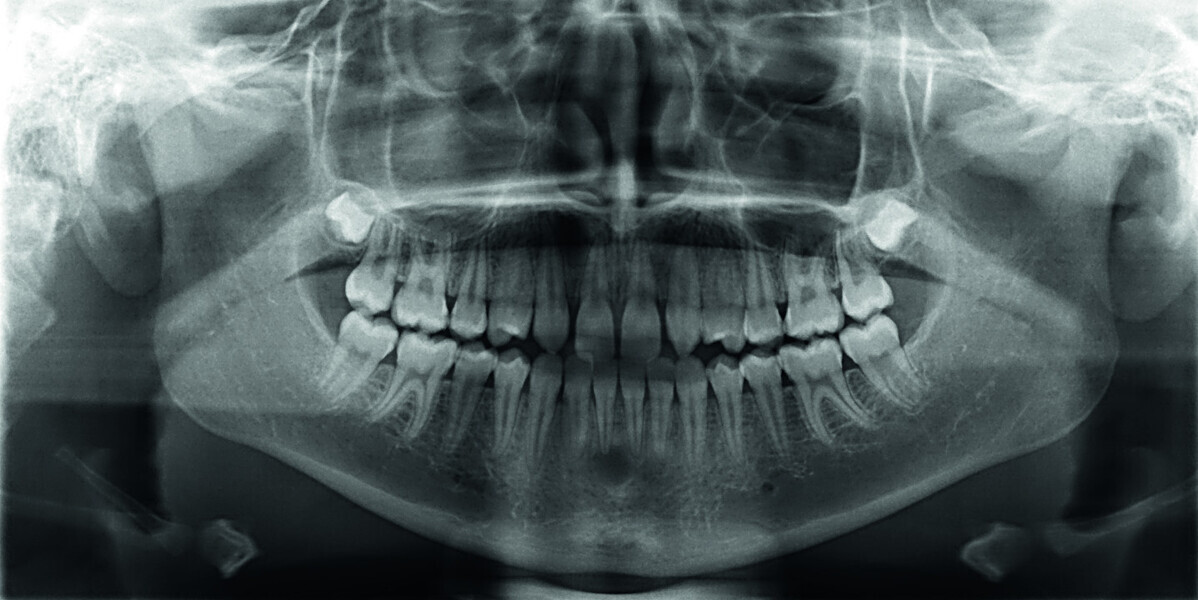

Orthodontic management of maxillary lateral incisors agenesis